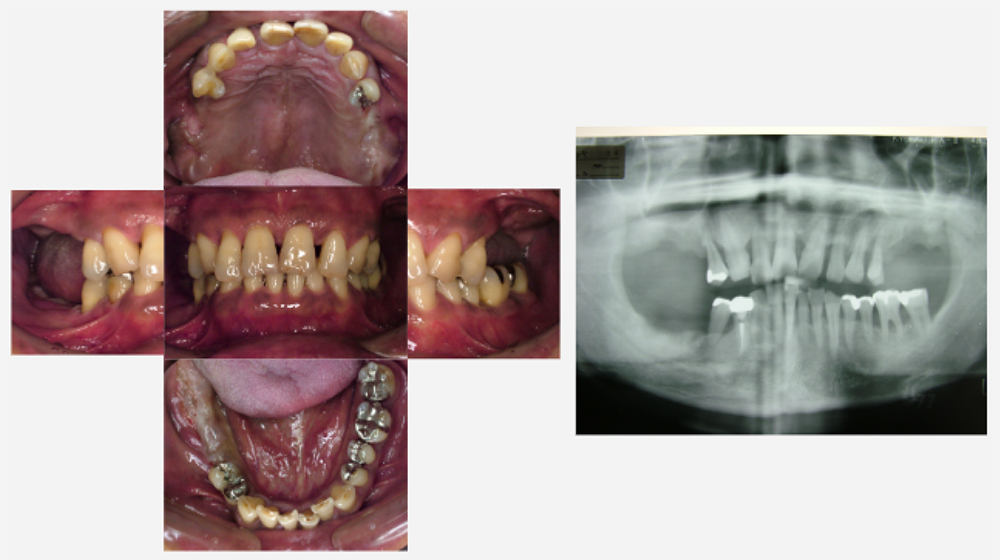

治療前治療後

| 治療内容 | インプラント奥歯1本・根管治療6歯 |

|---|---|

| 患者様の年齢 | 54歳 |

| 患者様の性別 | 女性 |

| 治療期間 | 2年 |

| 治療回数 | 根管治療合わせて70回程度 |

| 治療費用 | インプラント1歯 50万円/根管治療6歯 30万円 |

| 治療で得られるメリット |

|

| 治療する際に起こる リスク・副作用 |